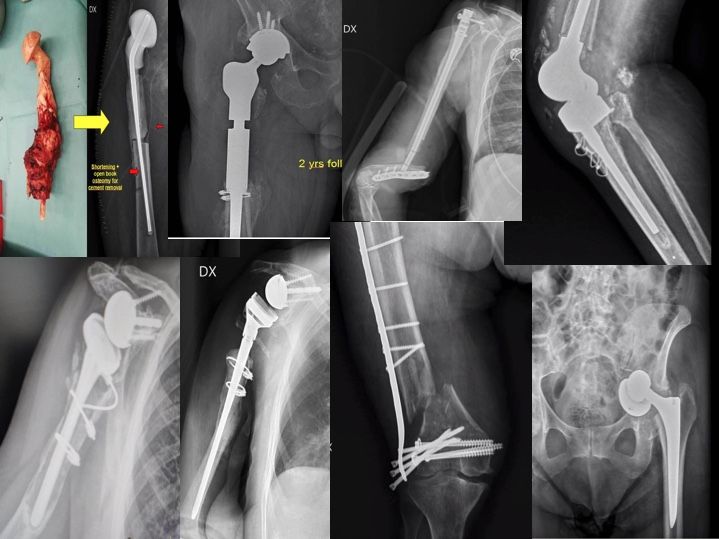

Chirurgia delle Infezioni e delle Complicanze ricostruttive in Ortopedia

La chirurgia ortopedica e traumatologica in questi decenni hanno compiuto passi enormi verso il futuro con nuove tecnologie sempre più “biologiche” e “computerizzate”, professionisti sempre più preparati e meticolosi hanno indiscutibilmente migliorato gli out comes di tanti interventi chirurgici. Tuttavia ancora oggi, alcune complicanze rappresentano ancora una sfida per il chirurgo ortopedico. A tutt’oggi una percentuale che si aggira mediamente tra l’1% ed il 4% degli interventi protesici possono presentare una complicazione tra cui la più temuta è senz’altro l’infezione ed analogamente anche nel campo traumatologico una percentuale di fratture va incontro a incomplete guarigioni, infezioni e deformità. Avere riferimenti, indicazioni e consigli può rappresentare un supporto per questi pazienti spesso già provati da precedenti lunghi trattamenti.